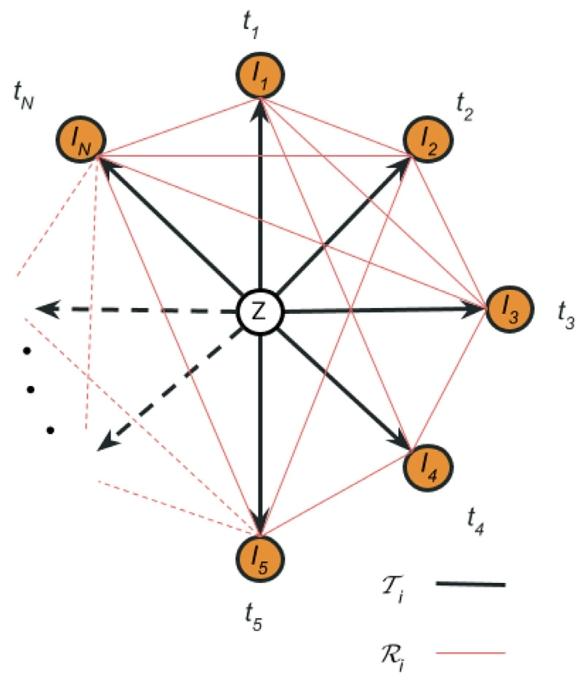

Fig. 1. The graph structure , where all timepoints ‘‘orbit’’ around the unobservedtemplate. In black, our choice of spanning tree of the graph, where all timepointsare connected through the template. The direction of the associated deformation fieldsis from the template to the timepoints, as indicated by the arrows In red, we drawthe observational graph describing the dense pairwise ‘‘noisy’’ registrations of alltimepoints. The direction of this transforms is arbitrary for each subject and knownthroughout the pipeline. The template is depicted at the centre of masses from alltimepoints, ignoring the notion of time between graph nodes. The distance betweentimepoints and the template and between the template themselves is kept equal torepresent the unbiasedness of the method, which treats all timepoints equally

图1 图结构,其中所有时间点围绕未观测模板“环绕”分布。黑色部分为我们选择的图的生成树,所有时间点通过模板相互连接。如箭头所示,相关形变场的方向为从模板指向时间点。红色部分为观测图,描述所有时间点的密集成对“带噪声”配准。对于每个受试者,该变换的方向是任意的,且在整个流程中已知。模板被绘制在所有时间点的质心位置,暂不考虑图节点间的时间概念。时间点与模板之间以及模板自身之间的距离保持相等,以体现该方法的无偏倚性——即对所有时间点一视同仁。